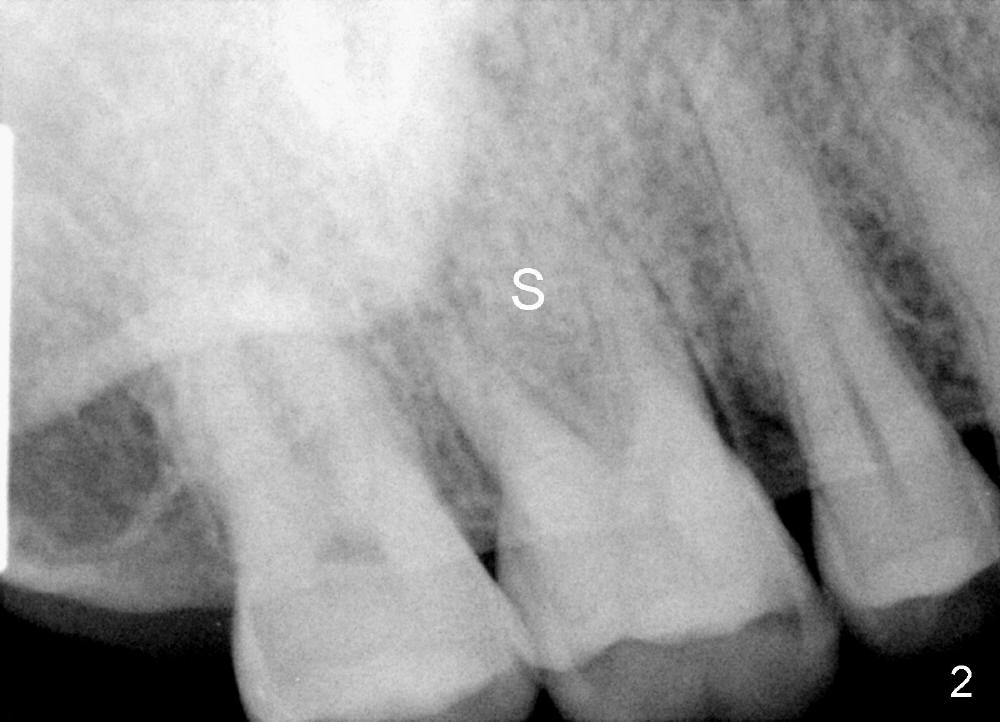

A 49-year-old man requests implant restoration of the upper 1st right molar with crack (Fig.1 ^).  He loves to chew nuts.  There is exosteotosis. In fact the upper left molar also has crown fracture.  Bone density should be high.  There is abundant bone all around.  The limiting factor will be the mesiodistal width of the septum (Fig.2 S), which is 4.87 mm.  Bone expansion may be required to place 5 mm implant.  The coronal part of the proximal surfaces of the implant may be exposed. Surgical handpiece may be needed to flatten the pointed coronal part of the septum before a 1.5 mm pilot drill is used to initiate ostetomy.  Bicon reamers are used to collect bone from the septum of #3.  Or osteotomes may be used to expand the osteotomy before implant placement.  Then place the autogenous bone with or without allograft back to the three remaining sockets and cover the thread exposed proximal surface.  The opening of the sockets will be covered by a collagen membrane, which is fixed between the crest level implant (5.0 mmx14 mm) and healing abutment (8 or 9 mm in diameter).  What happens in surgery?